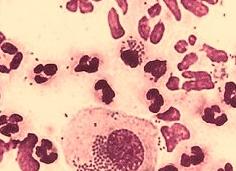

Гонококк Нейссера — грамотрицательный диплококк, внешне напоминающий два кофейных зерна, обращенных друг к другу вогнутой стороной. Они окружены микрокапсулой, жгутиков не имеют, спор не образуют. Гонококки были открыты ученым А. Нейссером в конце 19 века и получили одноименное название. Изучением морфологических, тинкториальных, культуральных, антигенных и биохимических свойств гонококков занимается частная микробиология, иммунология и эпидемиология.

- Тинкториальные свойства. Бактерии полиморфны: их клетки могут иметь бобовидную или палочковидную форму. Гонококки в мазке располагаются попарно, тетрадами и скоплениями.

- Бактериоскопическое исследование — приготовление, фиксация и окрашивание мазка метиленовым синим. При микроскопии гонококки имеют синий цвет, а остальные клетки — светло-голубой. В препаратах, окрашенных по Граму, обнаруживаются грамотрицательные диплококки, имеющие бобовидную форму.

Бактериологический метод исследования заключается в окрашивании материала специальным антисептиком Метиленовый синий, который окрашивает патоген в насыщенный голубой цвет. Следующий образец проходит исследование по Граму, что дает возможность отделить гонококки от других бактерий.

Гонококки (окраска метиленовым синим)